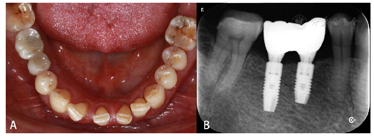

术后即刻拧入扫描杆,口内扫描数据导入DentalNavi软件,进行术后精度评价。结果显示45、46牙种植位置偏差均<0.3 mm,角度偏差<0.8°(图20)。

I期术后3个月复诊,患者自述种植区无明显不适,口内检查植体无明显松动,叩诊清音,牙龈愈合良好,X线检查种植体周围无明显阴影(图22),骨愈合良好。卸下愈合基台,穿龈形态良好,连接扫描杆进行口扫,氧化锆联冠修复,常规完成修复体制作与戴牙(图23)。

面观;B:颊面观

面观;B:颊面观术后6个月后随访,修复体稳定,黏膜未见红肿退缩,X线片牙槽嵴顶边缘骨未见明显吸收(图24)。